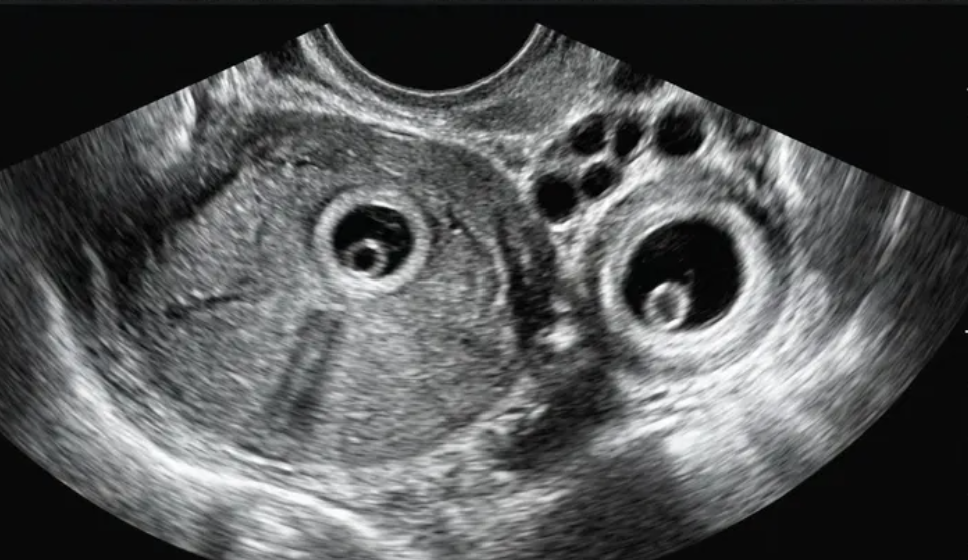

Gestação ectópica (US)

Ferramenta educacional baseada no NICE guideline NG126 (2019, atualização 2023), com abordagem conservadora. Ajuda a reconhecer sinais ultrassonográficos de gestação ectópica tubária e a lembrar a necessidade de correlação clínica e laboratorial.

Indica ectópica tubária (USTV)

Alta probabilidade (USTV)

Possível ectópica (USTV)